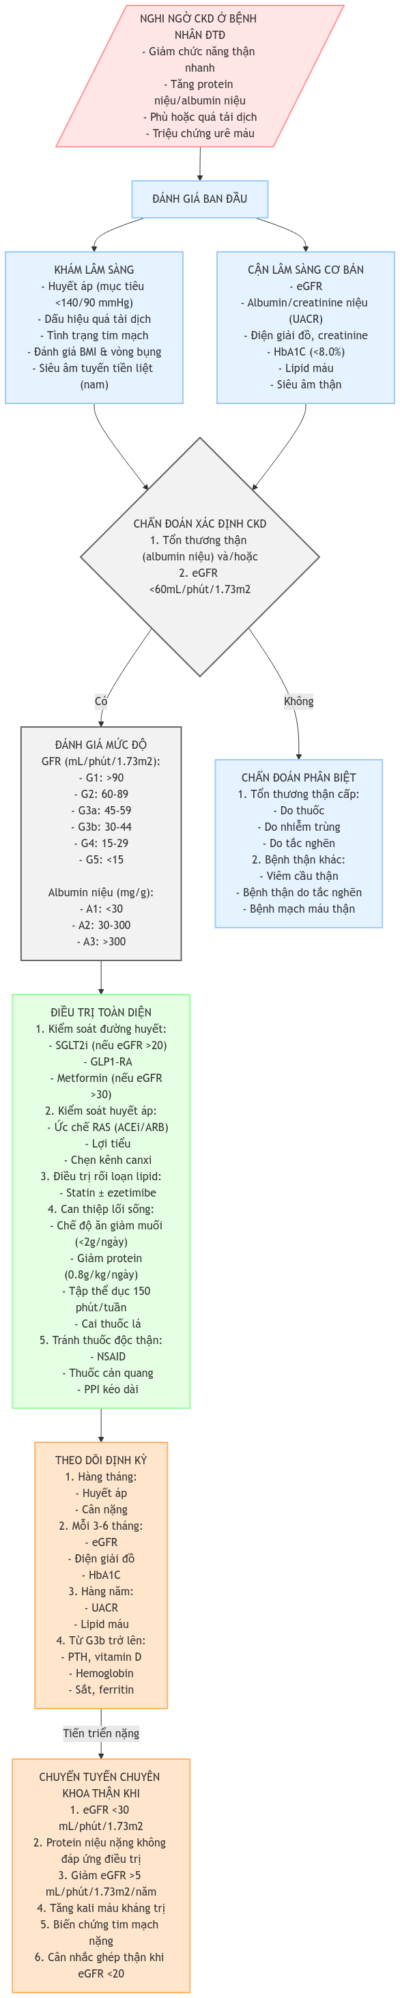

Quản lý Bệnh thận mạn ở Bệnh nhân Đái tháo đường

Quản lý Bệnh thận mạn ở Bệnh nhân Đái tháo đường (Chronic Kidn [...]